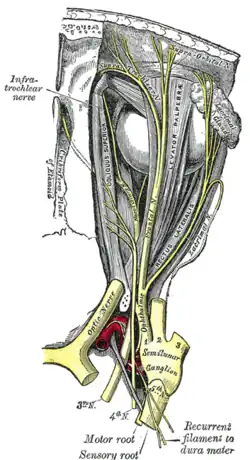

Nach langem intraduralen und dem längsten intrakraniellen Verlauf aller Hirnnerven verlässt der dünne N. IV die Schädelhöhle beim Menschen durch die Fissura orbitalis superior – bei Nicht-Primaten durch die entsprechende Fissura orbitalis, bei Paarhufern durch das Foramen orbitorotundum – und zieht über den Anulus tendineus communis hinweg in der Augenhöhle zu dem einzigen von ihm innervierten Muskel. Den orbitalen Verlauf begleiten auch afferente propriozeptive Fasern, die – wie bei den übrigen äußeren Augenmuskeln – über Verbindungen (Anastomosen) mit dem Nervus ophthalmicus zum Ganglion trigeminale gelangen.[1]

Die Sehne des Musculus obliquus superior wird in der Augenhöhle durch einen Rollknorpel in ihrer Zugrichtung abgelenkt. Dieser Rollknorpel (Trochlea) war für den Nerven namensgebend.